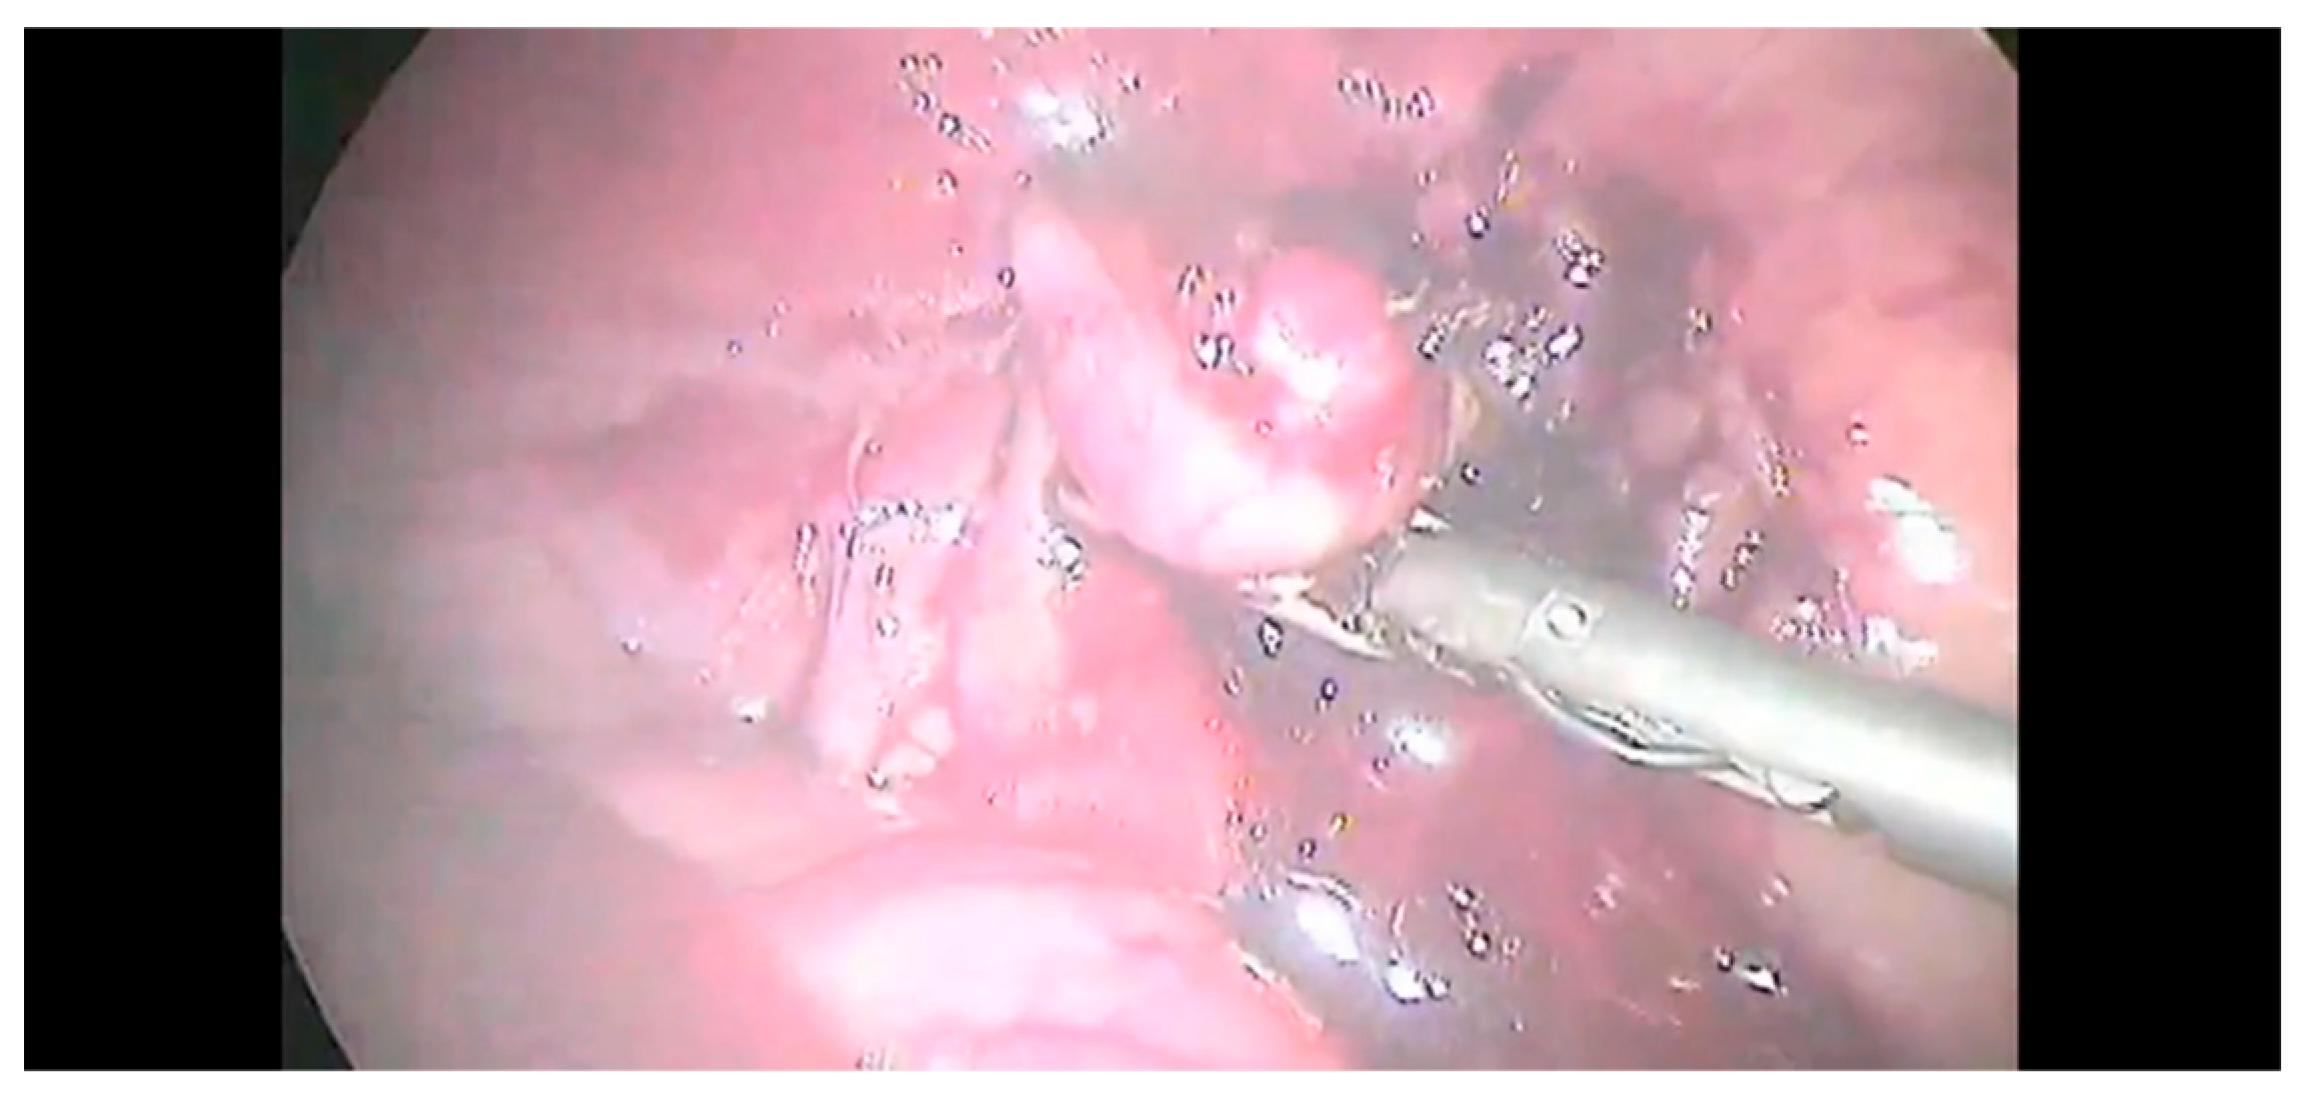

The adrenal gland was dissected from the fibrous tissue attached to vena cava. The risk of capsule rupture was limited through the careful manipulation of the gland and surrounding fat. The capsule of the right-side masses was continuous with the tunica externa of the vena cava; hence, the dissection was initiated between the mass and the vena cava. Then, the dissection was continued as described for left-side lesions. Once the dissection was completed (Figure 5), the adrenal gland was removed with a surgical glove or retrieval bag to minimize the neoplastic cells spared from the T2.

Figure 5.

Complete dissection of the adrenal gland.